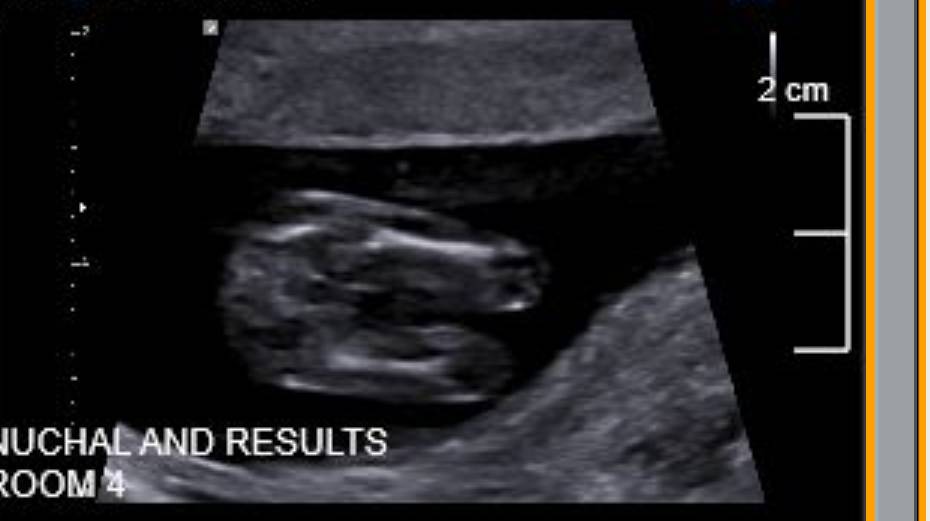

Hi all, the ultrasound technician wouldn't tell me what she thought - am dying to know. Please help!! Attachment 42099Attachment 42100Attachment 42101Attachment 42103

Unfortunately potty shots at 13 weeks aren't reliable and that's why the tech woudln't give an opinion. Do you have any nub shots (taken from the side?)

Looks girly but not greatly reliable at this stage. Mine were accurate though and looked similar to yours and I had a girl.

Thanks so much, I completely respect the sonographer for not speculating, am just so curious. Here is the only other shot that is vaguely sideways but I can't tell if it is showing the nub or not. Any thoughts greatly appreciated. Attachment 42109

Yeah, the upsidedown shots are no good unfortunately, plus the nub is not really clear in that one. I hope you get what you're wishing for!